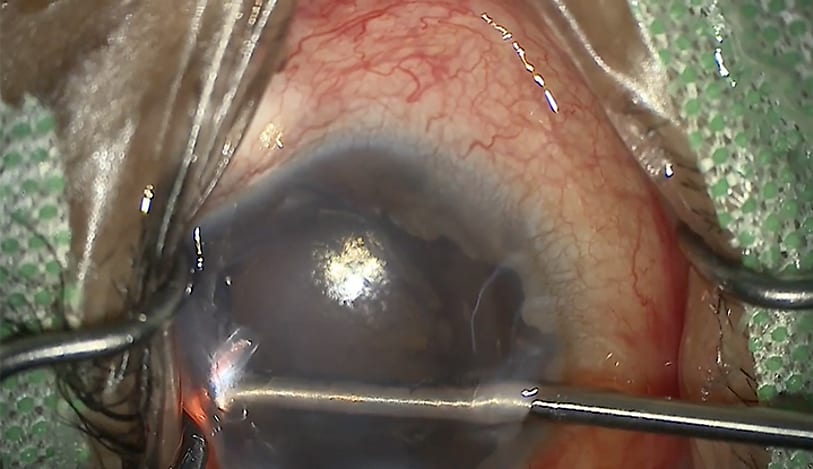

Glaucoma Group Therapy Video: Complications in Canaloplasty